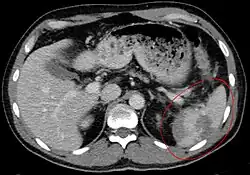

Traumatic rupture of the spleen on contrast enhanced axial CT (portal venous phase)

Splenic hematoma resulting in free abdominal blood